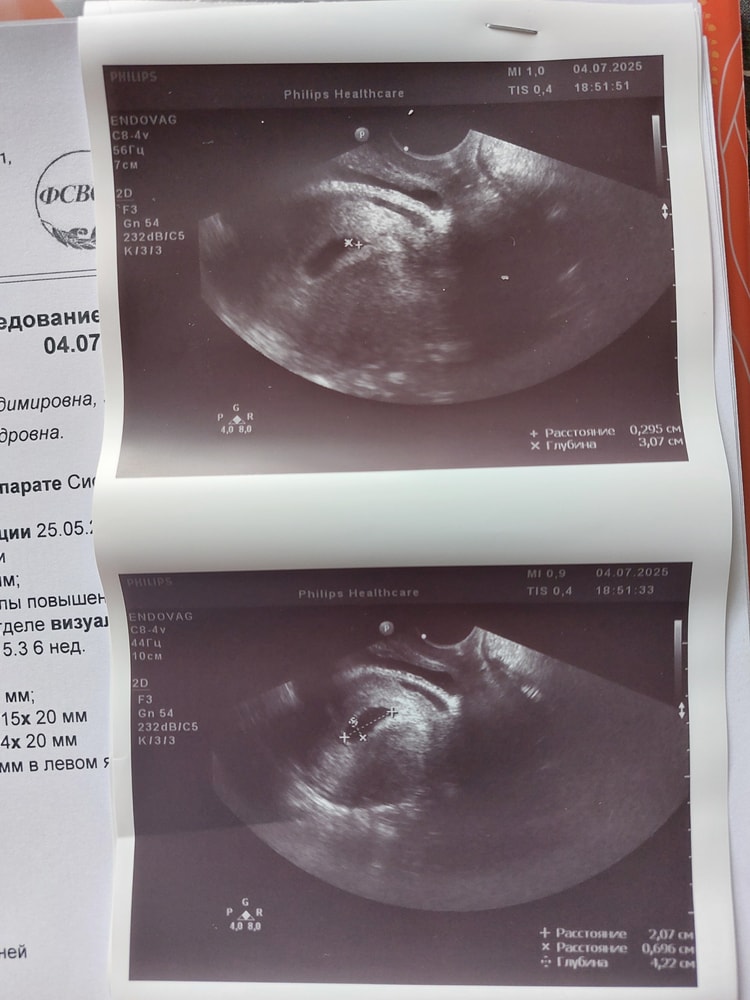

Была на УЗИ в пятницу, это была 5 неделя и 5 дней. Сходила не к своему постоянному врачу, а просто к ближайшему, и пожалела об этом, потому что аппарат оказался похуже, чем в моей любимой клинике.

Итог: отслоек и гематом нет. Есть плодное яйцо вытянутой формы, СВД 15 мм + желточный мешок 3 мм. Эмбрион врач не разглядела. Сказала, "перекрывается желточным мешочком", а в заключении написала "чётко не визуализируется".

Ей не понравилось, что плодное яйцо уже хорошего размера, а эмбриона не видно, поэтому сказала сдать кровь на ХГЧ с промежутком 48 ч, чтобы исключить неразвивающуюся беременность. Пойду сдавать завтра.